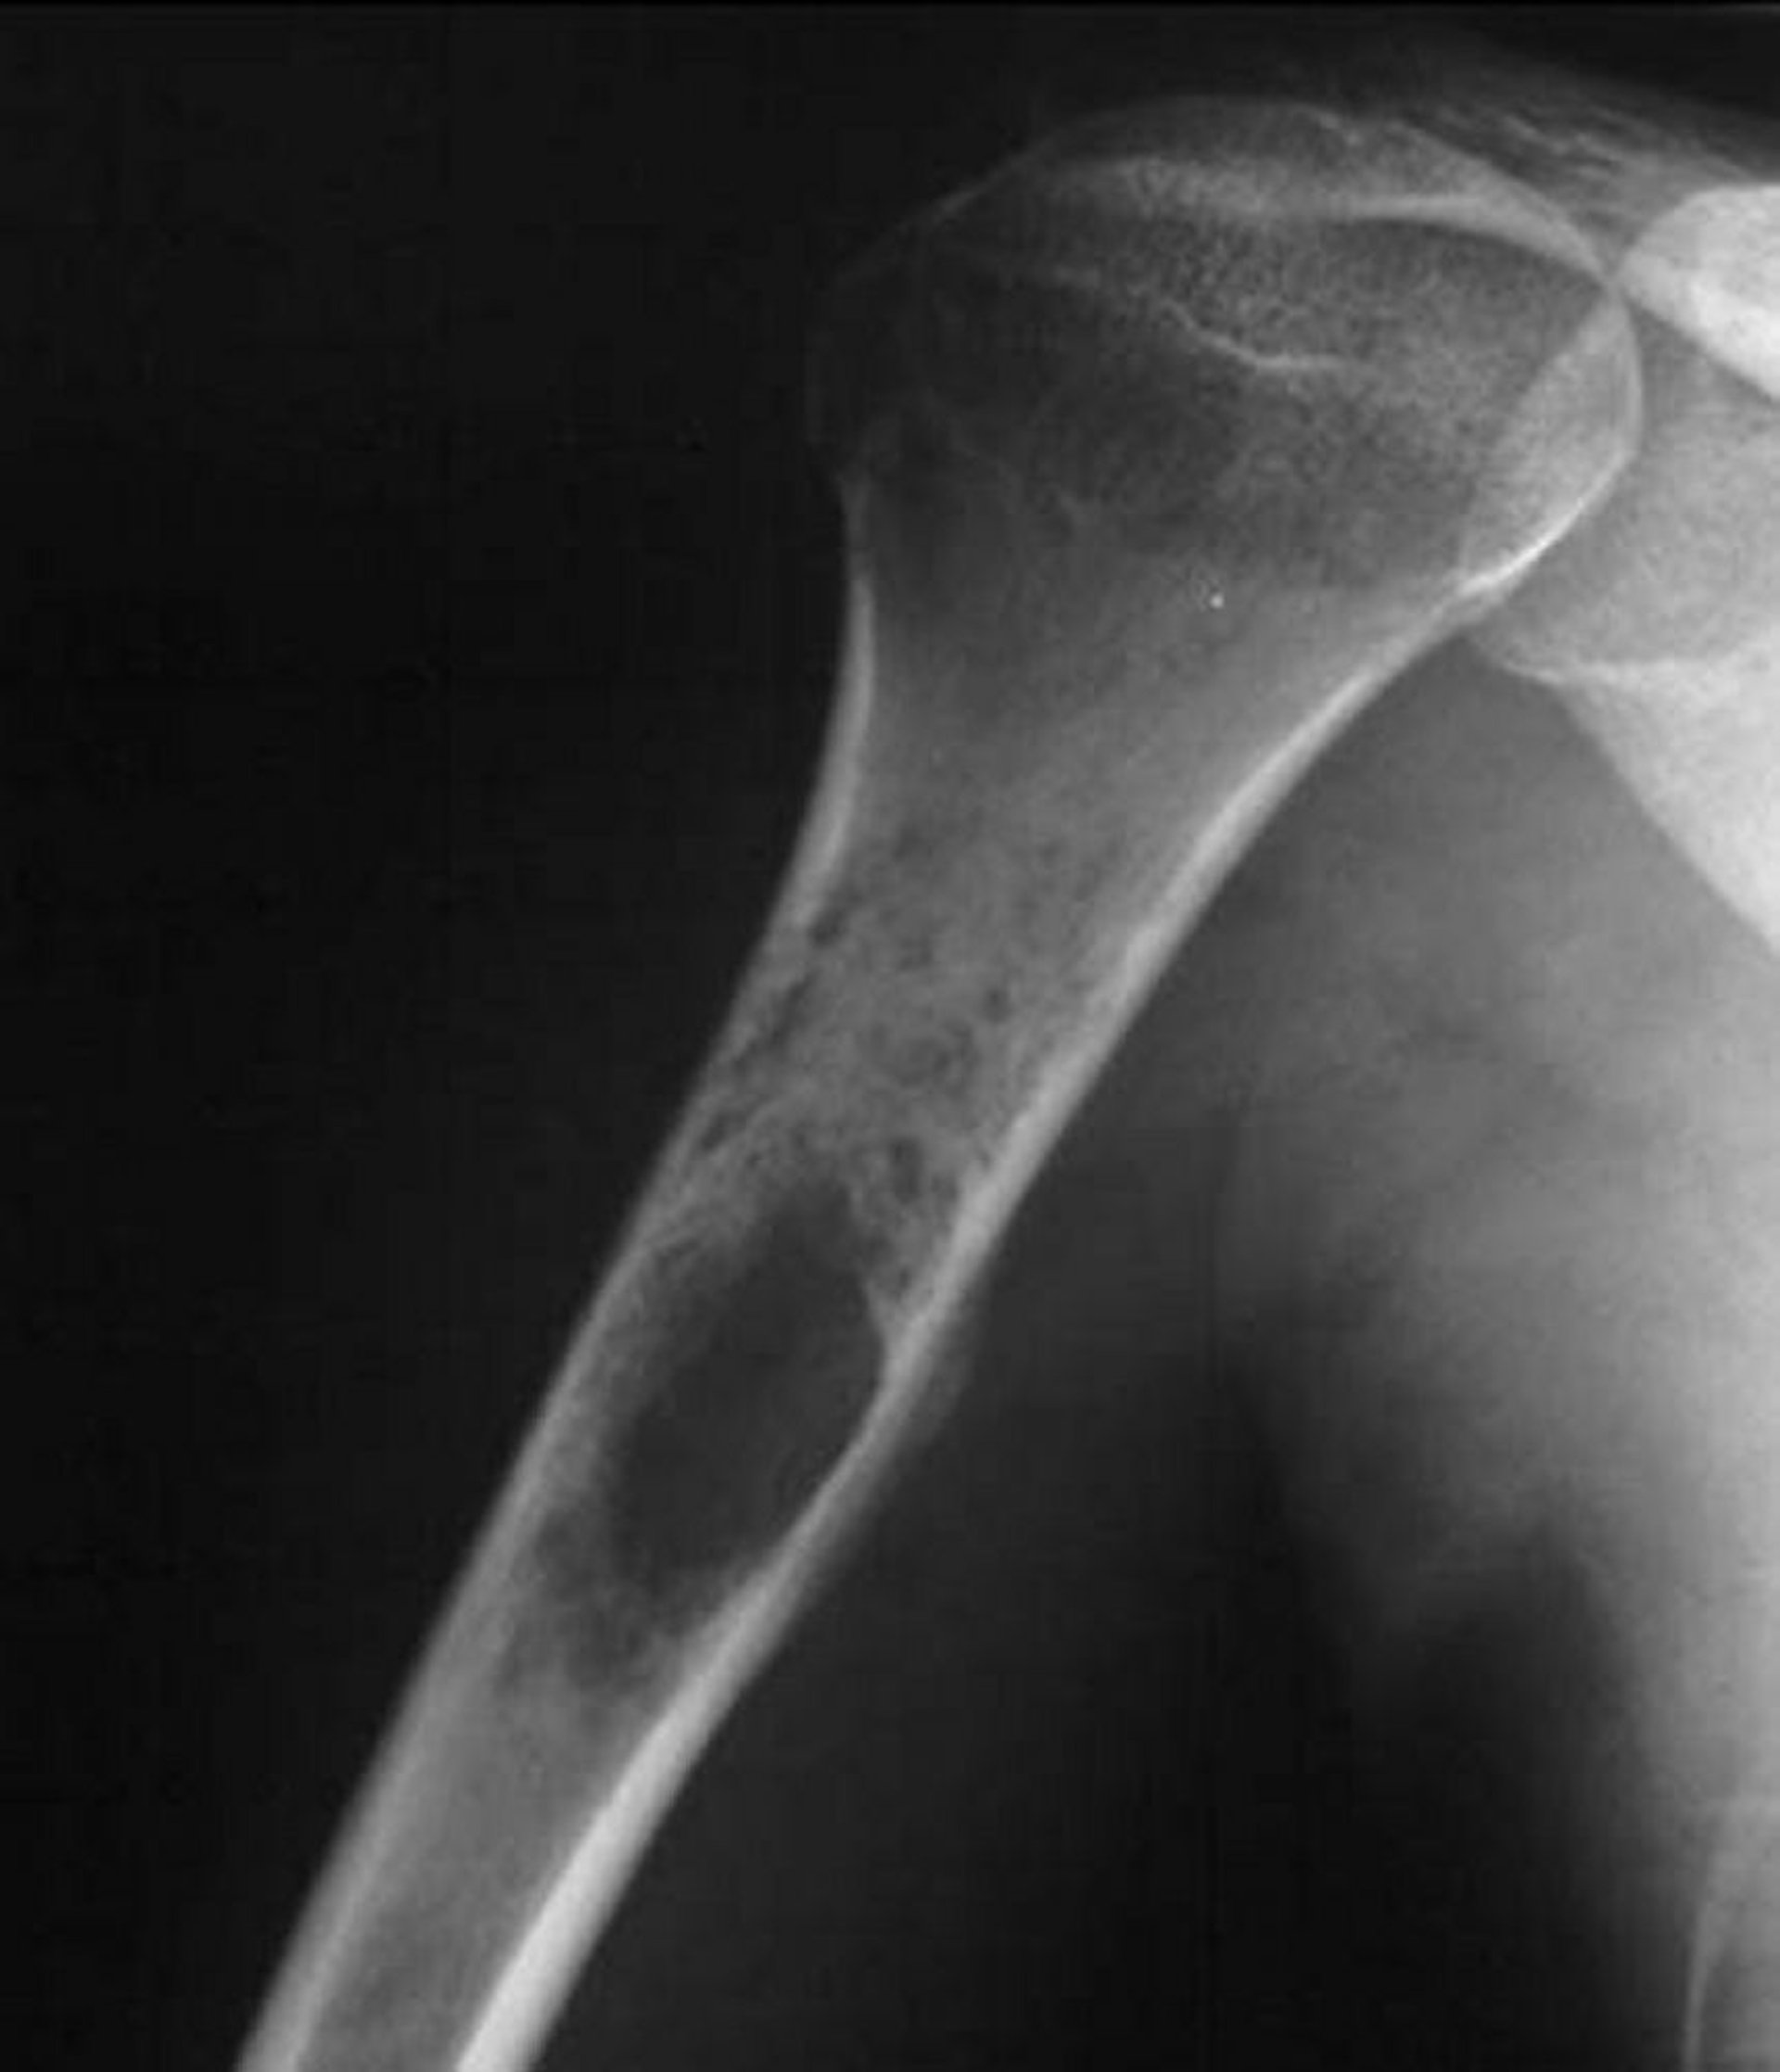

Sarcoma de Ewing óseo

Esta radiografía de hombro muestra un tumor destructivo permeativo que surge en el húmero proximal, lo cual es típico del sarcoma de Ewing.

Image courtesy of Michael J. Joyce, MD, and Hakan Ilaslan, MD.